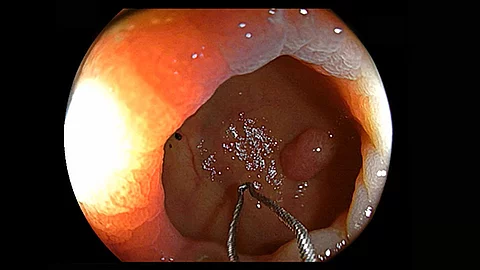

Unser neues Endoskopie-Video zeigt einen offensichtlichen Befund, der aber auch leicht zu übersehen ist. Welcher das ist und welche Methode zur Behandlung angewandt wurde, präsentiert PD Dr. Jochen Weigt vom Uniklinikum Magdeburg.